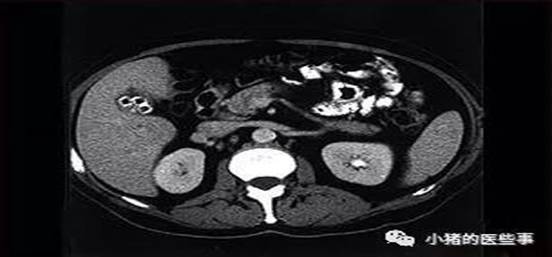

超声、X线、CT、MRI,该如何选择? 无论是看病还是体检,影像学检查总是非常重要的一部分。 超声、X线、CT、MRI,面对多种的检查,有没有产生一些困惑?这个检查是什么?为什么要选这个?为什么做了这个还要做那个?检查是越贵越好吗?...... 如何能根据自身情况,选择最适合的检查项目?专家告诉你每个检查是什么!如何选择检查!如何完成好检查! 一、【检查原理】 超声: [切面里看回声]。超声波穿透人体时产生反射波,收集该反射波信息进行成像,反映该切面内的结构,*用探头获取切面可以对任意切面进行检查*。 X线: [压扁透视看]。就像先将身体压扁,再发射X线穿过人体,由于身体结构的密度厚度对X线阻挡程度不同,最后投射在底片上射线量不同,经过处理形成图像,获得的图像是所有结构的重叠,*按射线发射前至后方向成像*。 CT: [切片透视看]。射线的原理与X线相似,不同的是将身体进行“切片”,显示每一切面里的结构,而不是X线的压缩重叠,*可从正面/侧面/横断进行切片成像*。 MRI(磁共振): [切片看原子运动]。人体内不同结构包含不同量的氢原子,人体进行MRI检查时,相当于体内的氢原子在磁场内进行运动,收集氢原子的运动信息进行切面成像,*正面/侧面/横断进行切片成像*。 二、【如何选择检查】。 不同部位适合的检查不同,下表是各部位与各检查的选择优先度: (没时间可以只看上图) 骨头:首选X线,进一步观察可做CT、MRI可观察里面出血及病变成分情况。 心脏:看心功能及结构首选超声、MRI可观察结构内病变。 腹部及盆部:包括肝胆胰脾肾肠子宫卵巢前列腺等,X线可初步排查胃肠是否穿孔,超声观察除肠管外的实性器官效果好,CT可更进一步明确病灶,MRI更适合对病变成分进行分析鉴别。 胸部:X线是首先要做,进行筛查CT显示效果最好。 皮表包块:指长在表浅部位的小包块,超声是首选,MRI也可对稍大的包块进行分析。 血管:浅表血管(四肢和颈部)超声好,深部血管(大脑及心、胸、腹部)CT好。 浅表器官:包括乳腺和甲状腺腮腺等等,超声是首选,MRI也可分析鉴别,其中X线中的钼靶是乳腺检查的重要部分。 脑及神经:MRI是首选,超声可初步检查表浅的神经。 以下是你们关注的费用和辐射等问题: 三、【如何做好检查】 是否禁食及需要大量喝水?与检查方式无关,与检查部位有关,腹部检查需要禁食6小时以上;腹部检查可在检查前大量饮水;泌尿系检查需要多喝水憋尿。 保持静止,进行检查时不要说话不要动,身体尽可能保持静止(就像你拍照时,动就会模糊~这个道理)。 动作配合。为了更好显示结构,做不同部位检查时,常要配合工作人员做特定动作,超声腹部检查常需要憋气鼓起肚子;颈椎X线检查常需要头后仰前伸张口。4大检查的特点都不一样,医生会根据实际情况进行选择。相信医生,好好配合,你会获得最好的效果! |